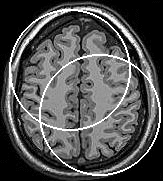

Segmentation of an MRI brain image, using two level set functions to represent the evolving contours